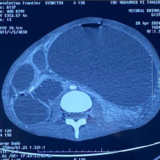

Figure 2 : Image scanographique montrant un cæcum distendu et basculé au niveau de l’hypochondre gauche.

Figure 3 : Coupe frontale du scanner montrant le signe du tourbillon (whirl sign).

Scanner abdominal (TDM) :

Le scanner a révélé une distension de l’intestin grêle située en amont de deux « signes du bec » (beak signs) contigus. Ce tableau clinique est compliqué par un volvulus du cæcum par torsion, avec la présence caractéristique d’une image en tourbillon (whorl sign), sans que des signes de complications majeures ne soient visibles à ce stade.